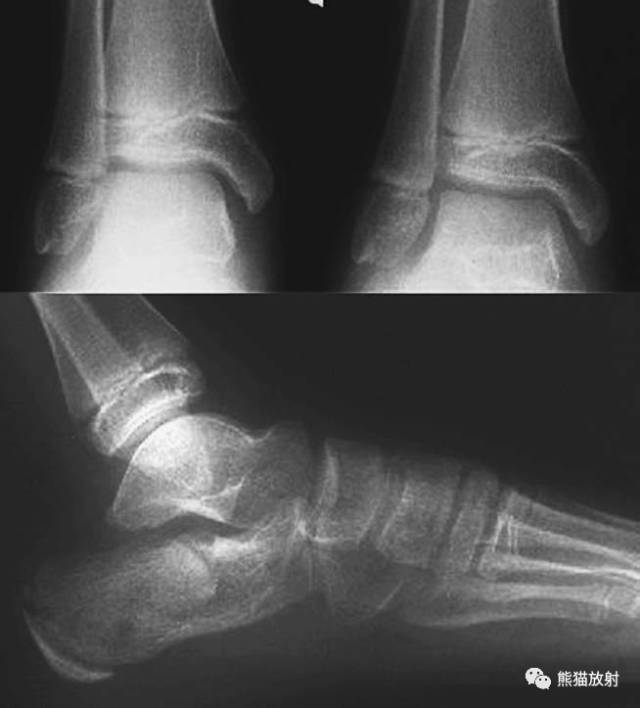

(上图)骨骺轻微向背侧、内侧移位,1-2周后随访骺板处可见成骨反应。

Salter-Harris I型:干骺端及骨骺分离

平片通常为正常,可表现为骺板增宽或骨骺轻度移位。